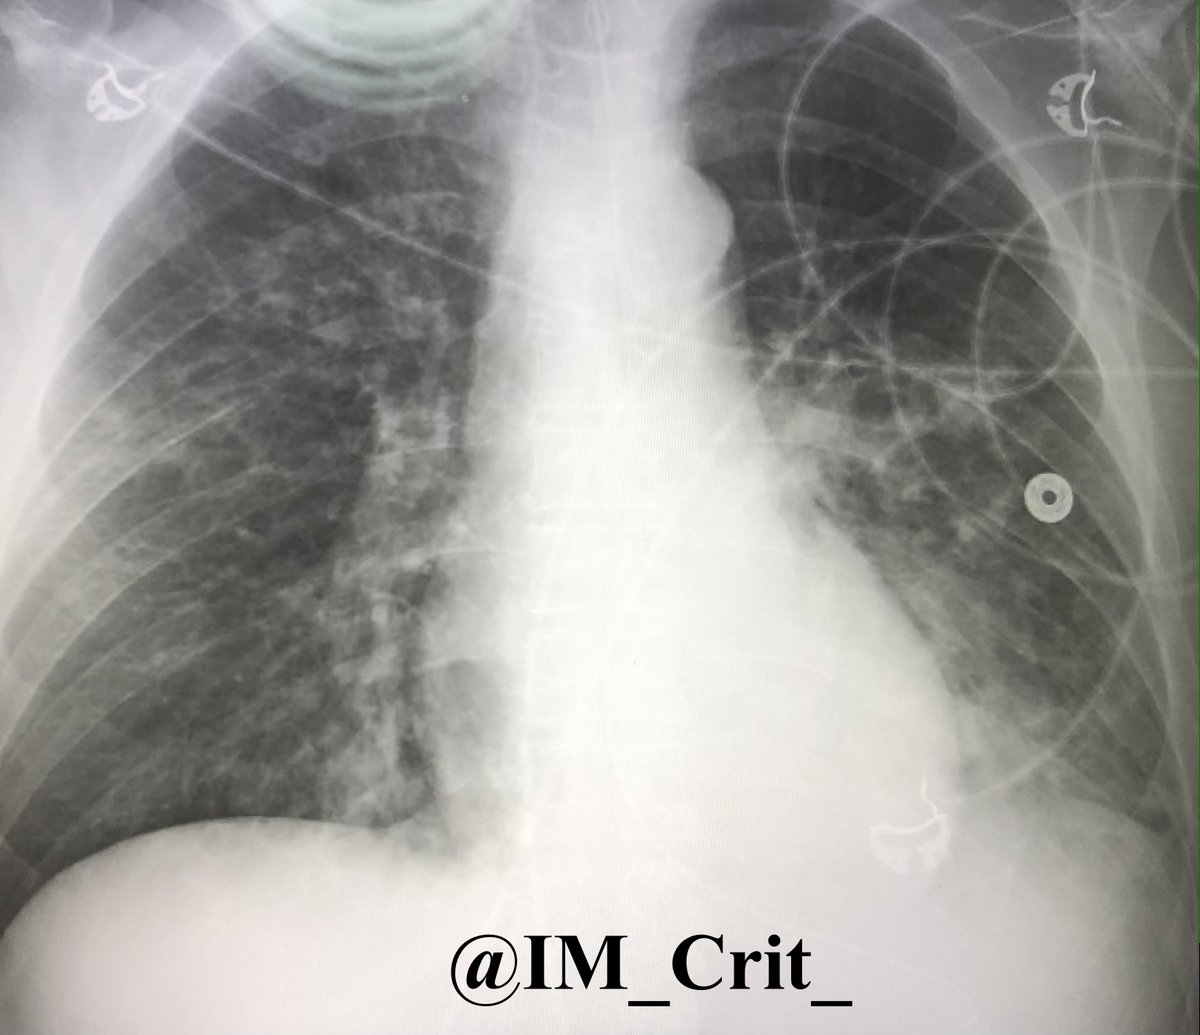

Unfortunately, it seems that patient had already aspirated. A few hours later & while his mental status had began to improve, he had to be intubated for "ARDS" picture. Empiric antibiotics were started. The admission CXR in the outside hospital was

& got worse w additional aspiration. Pt stayed on the vent for 5 ds. Also developed vasodilatory shock requiring norepi/vasopressin drips for 3 ds (I am skipping POCUS findings, sorry!) as well as AKI requiring CRRT. Eventually, he improved & was extubated. RUE weakness resolved.